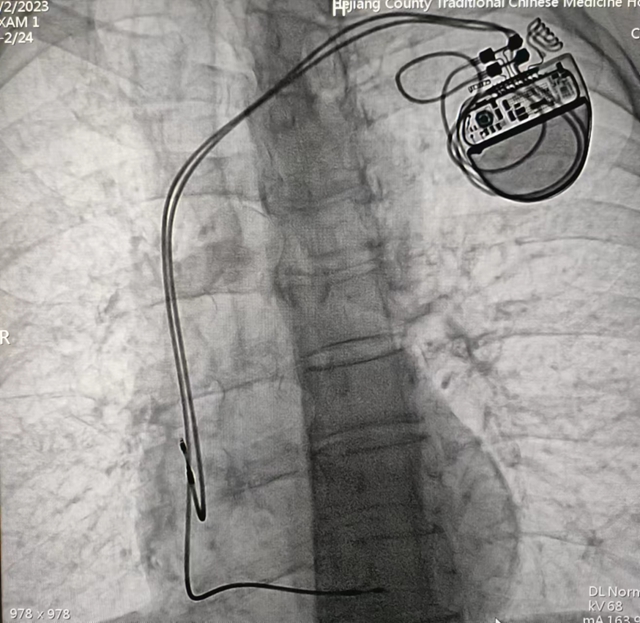

合江縣中醫(yī)醫(yī)院:零突破!3例心臟人工永久雙腔起搏器植入術(shù)成功開展

近日,合江縣中醫(yī)醫(yī)院心血管內(nèi)科成功為3位高齡心動過緩患者植入人工永久雙腔起搏器,實現(xiàn)了醫(yī)院心臟永久雙腔起搏器安置術(shù)零突破,為患者心臟裝上“保險”!

患者男性,67歲,突發(fā)暈厥入院,心電圖提示為三度房室傳導(dǎo)阻滯。

經(jīng)心血管內(nèi)科團隊綜合評估,確定該患者有行心臟永久人工起搏器植入指征??剖抑魅吸S勝立即與患者家屬溝通,并告知相對風(fēng)險后,家屬考慮后,同意心血管內(nèi)科團隊為家屬行心臟永久人工起搏器植入手術(shù)。

經(jīng)過充分的術(shù)前準(zhǔn)備,由心血管內(nèi)科主任黃勝主刀,在介入醫(yī)學(xué)中心醫(yī)護團隊默契配合下,成功為患者行永久性心臟起搏器植入術(shù)。手術(shù)歷經(jīng)1小時左右順利完成,起搏器感知、起搏功能良好,患者生命體征平穩(wěn)。近日,科室又為兩名患者成功開展了此手術(shù)。